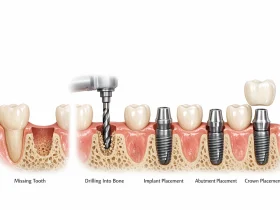

مراحل ایمپلنت دندان به طور کلیایمپلنت دندان یکی از بهترین روشهای جایگزینی دندانهای از دست رفته است ...